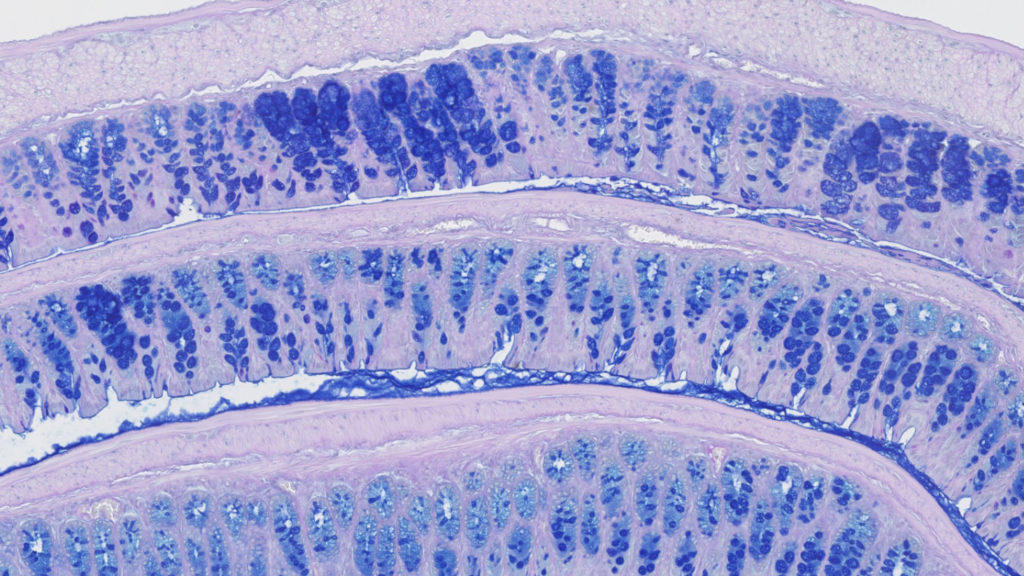

Preclinical solutions for ulcerative colitis & Crohn’s disease research

For teams developing new treatments for gut inflammation, one of the biggest hurdles is identifying a preclinical model that truly fits the targeted disease and therapeutic strategy. As no single model reflects the full complexity of human inflammatory gut disease, choosing the right approach depends on the question you want to answer. Acute models may help you screen for activity, while chronic or immune-mediated models allow you to explore mechanism, durability, or combination effects. Understanding these nuances early can accelerate decision-making and reduce unnecessary iterations.

In this service sheet, we introduce the spectrum of colitis models available at Oncodesign Services and explain how we support your project from model selection to data interpretation. By combining established protocols, reproducible endpoints, and translational expertise, we help researchers build solid, clinically relevant foundations for their gastrointestinal inflammation programs.